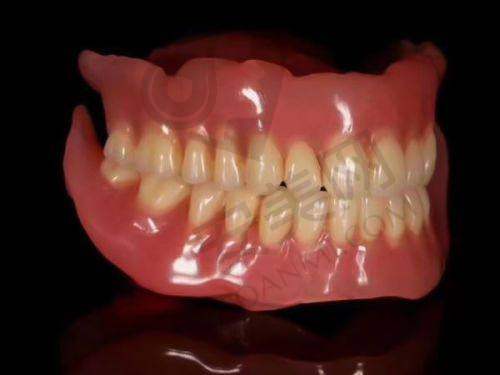

韩国登腾种植牙适合大多数牙齿缺失的患者,无论是单颗牙齿缺失、多颗牙齿缺失还是全口牙齿缺失都可以考虑。对于那些对牙齿美观和咀嚼功能有较高要求的患者来说,种植牙是一个不错的选择。不过,患者的牙槽骨条件需要满足一定的要求,如果牙槽骨骨量不足,可能需要精良行骨增量手术。此外,患者的身体状况也需要符合手术的要求,如没有重度的全身性疾病等。